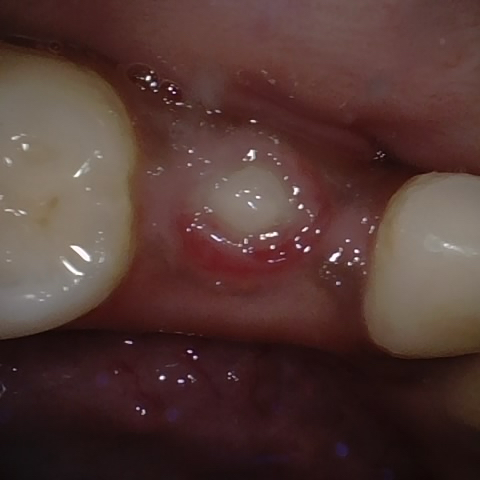

Annotated as "Good"